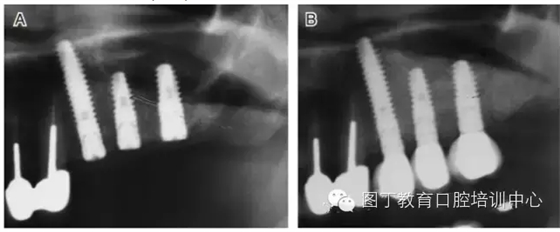

病例8 多顆種植體植入(圖10)

圖10